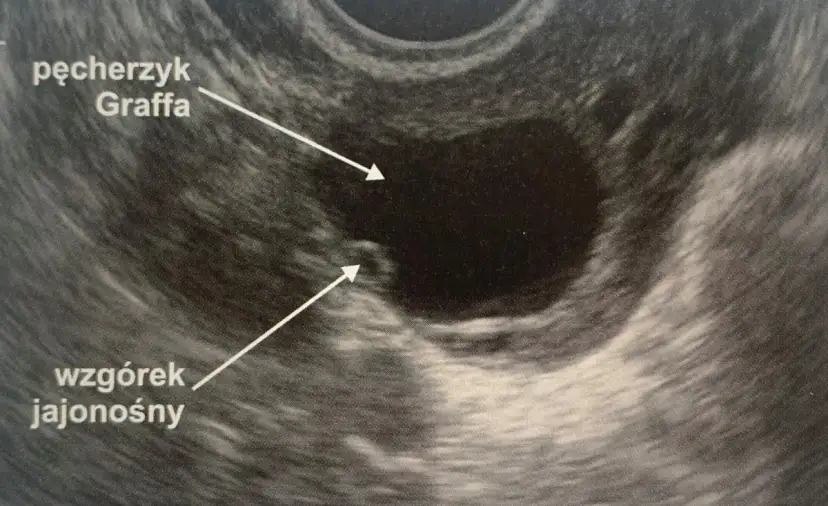

Pęcherzyk 18 mm: dowiedz się, kiedy nastąpi owulacja i jak precyzyjnie zaplanować starania o dziecko. Sprawdź rolę endometrium i hCG!